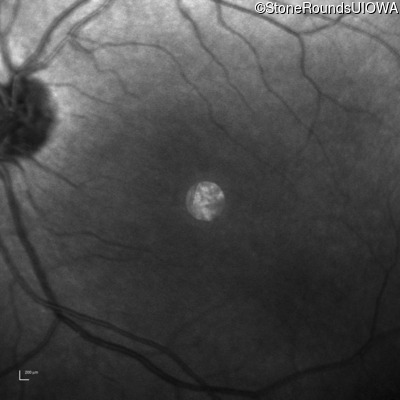

Infrared Fundus Photograph - Right - 10/200

Exemplar

Infrared Fundus Photograph - Left - 10/100